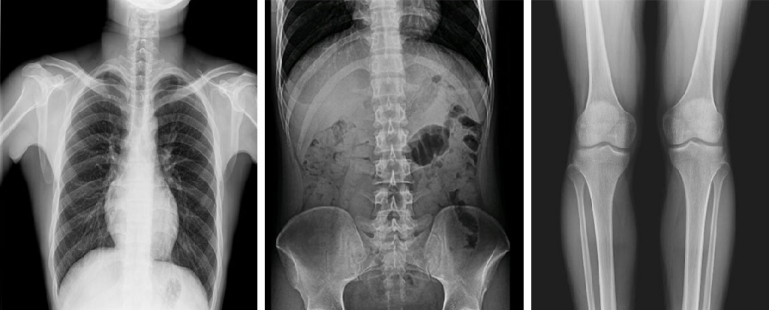

而且,影像采集幅面大,17×17英寸超大視野可覆蓋成年人的全胸全腹,并且能在連續(xù)動(dòng)態(tài)中實(shí)時(shí)高清點(diǎn)片,從而達(dá)到精準(zhǔn)診斷的目的。設(shè)備靈活高效的多維度運(yùn)動(dòng)設(shè)計(jì),也帶來(lái)了更加智能化、人性化操作體驗(yàn),可大幅提升檢查效率。

與此同時(shí),普利德動(dòng)態(tài)平板DRF還具有全身拼接功能,尤其適用于全脊柱和全下肢攝影,為臨床提供高精度圖像,輔助脊柱畸形矯形治療、康復(fù)檢查。